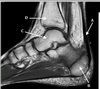

5

Perfectly

12

Q

What is letter B?

A

BICEPS TENDON (LONG HEAD)

How well did you know this?

1

Not at all

2